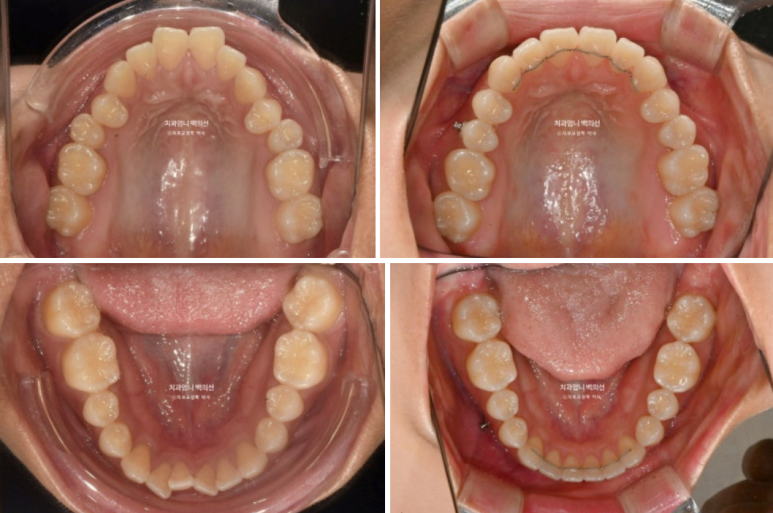

삐뚤한 치아 배열은 사랑니 공간을 이용해서 어금니를 뒤로 밀어내어 해결하기로 하고 앞니 개방교합은 어금니 함입을 통해 해결하기로 합니다.

어금니 함입은 입천장에 교정용 나사 미니스크류를 심어 도모하기로 합니다.

사랑니 공간으로의 후방이동 역시 미니스크류가 필요하죠.

악궁확장에 대해서는 악궁이 좁은 게 아니라 단순히 첫번째 작은어금니가 입천장으로 기울어진 상황이라 악궁확장은 따로 하지 않습니다.

교정용 나사는 위 2개 아래 2개 총 4개를 식립해서 진행했습니다.

첫번째 세트 51개 장치 안에서 미니스크류를 이용한 상악 어금니 합입과 하악 어금니 후방이동이 잘 일어났습니다.